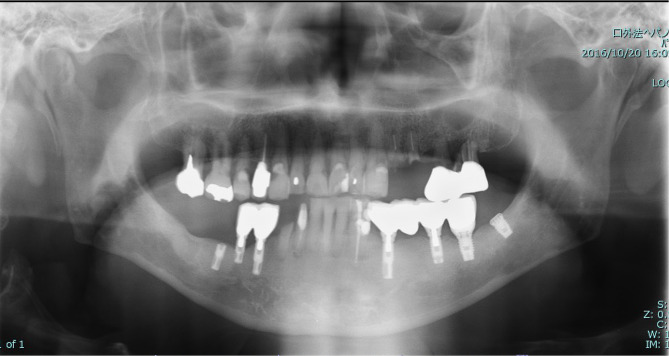

Case presentation: An 81-year-old male patient with Parkinson's disease presented to our outpatient clinic with bruxism and crossbites. FIPs, with five Brånemark system implants, were placed in the bilateral lower molars. The FIP was replaced with an IOD with two locator attachments to create an oral environment that was easier for caregivers to clean and allow easy recovery of masticatory function if residual teeth were fractured in the care environment. As his systemic condition deteriorated, treatment was changed from outpatient to in-home visits. During dental care visits, professional oral cleaning and denture repair were continued, and good nutritional status was maintained. However, the patient developed cholecystitis and was hospitalized. During hospitalization, gastrostomy was performed because he developed aspiration pneumonia. After discharge from the hospital, the patient remained in bed all day and could not wear an IOD, resulting in buccal mucosa ulceration due to abrasion of the locator abutment. We decided to replace the abutment with cover screws; however, not all the implants could sleep submucosally. Although regular oral cleaning was resumed, new ulcers developed even when cover screws were installed. Additionally, swelling and drainage were observed at the peri-implant mucosal site where peri-implantitis had once occurred during an outpatient visit. The patient was readmitted to the hospital for a urinary tract infection, and subsequent visits were abandoned.